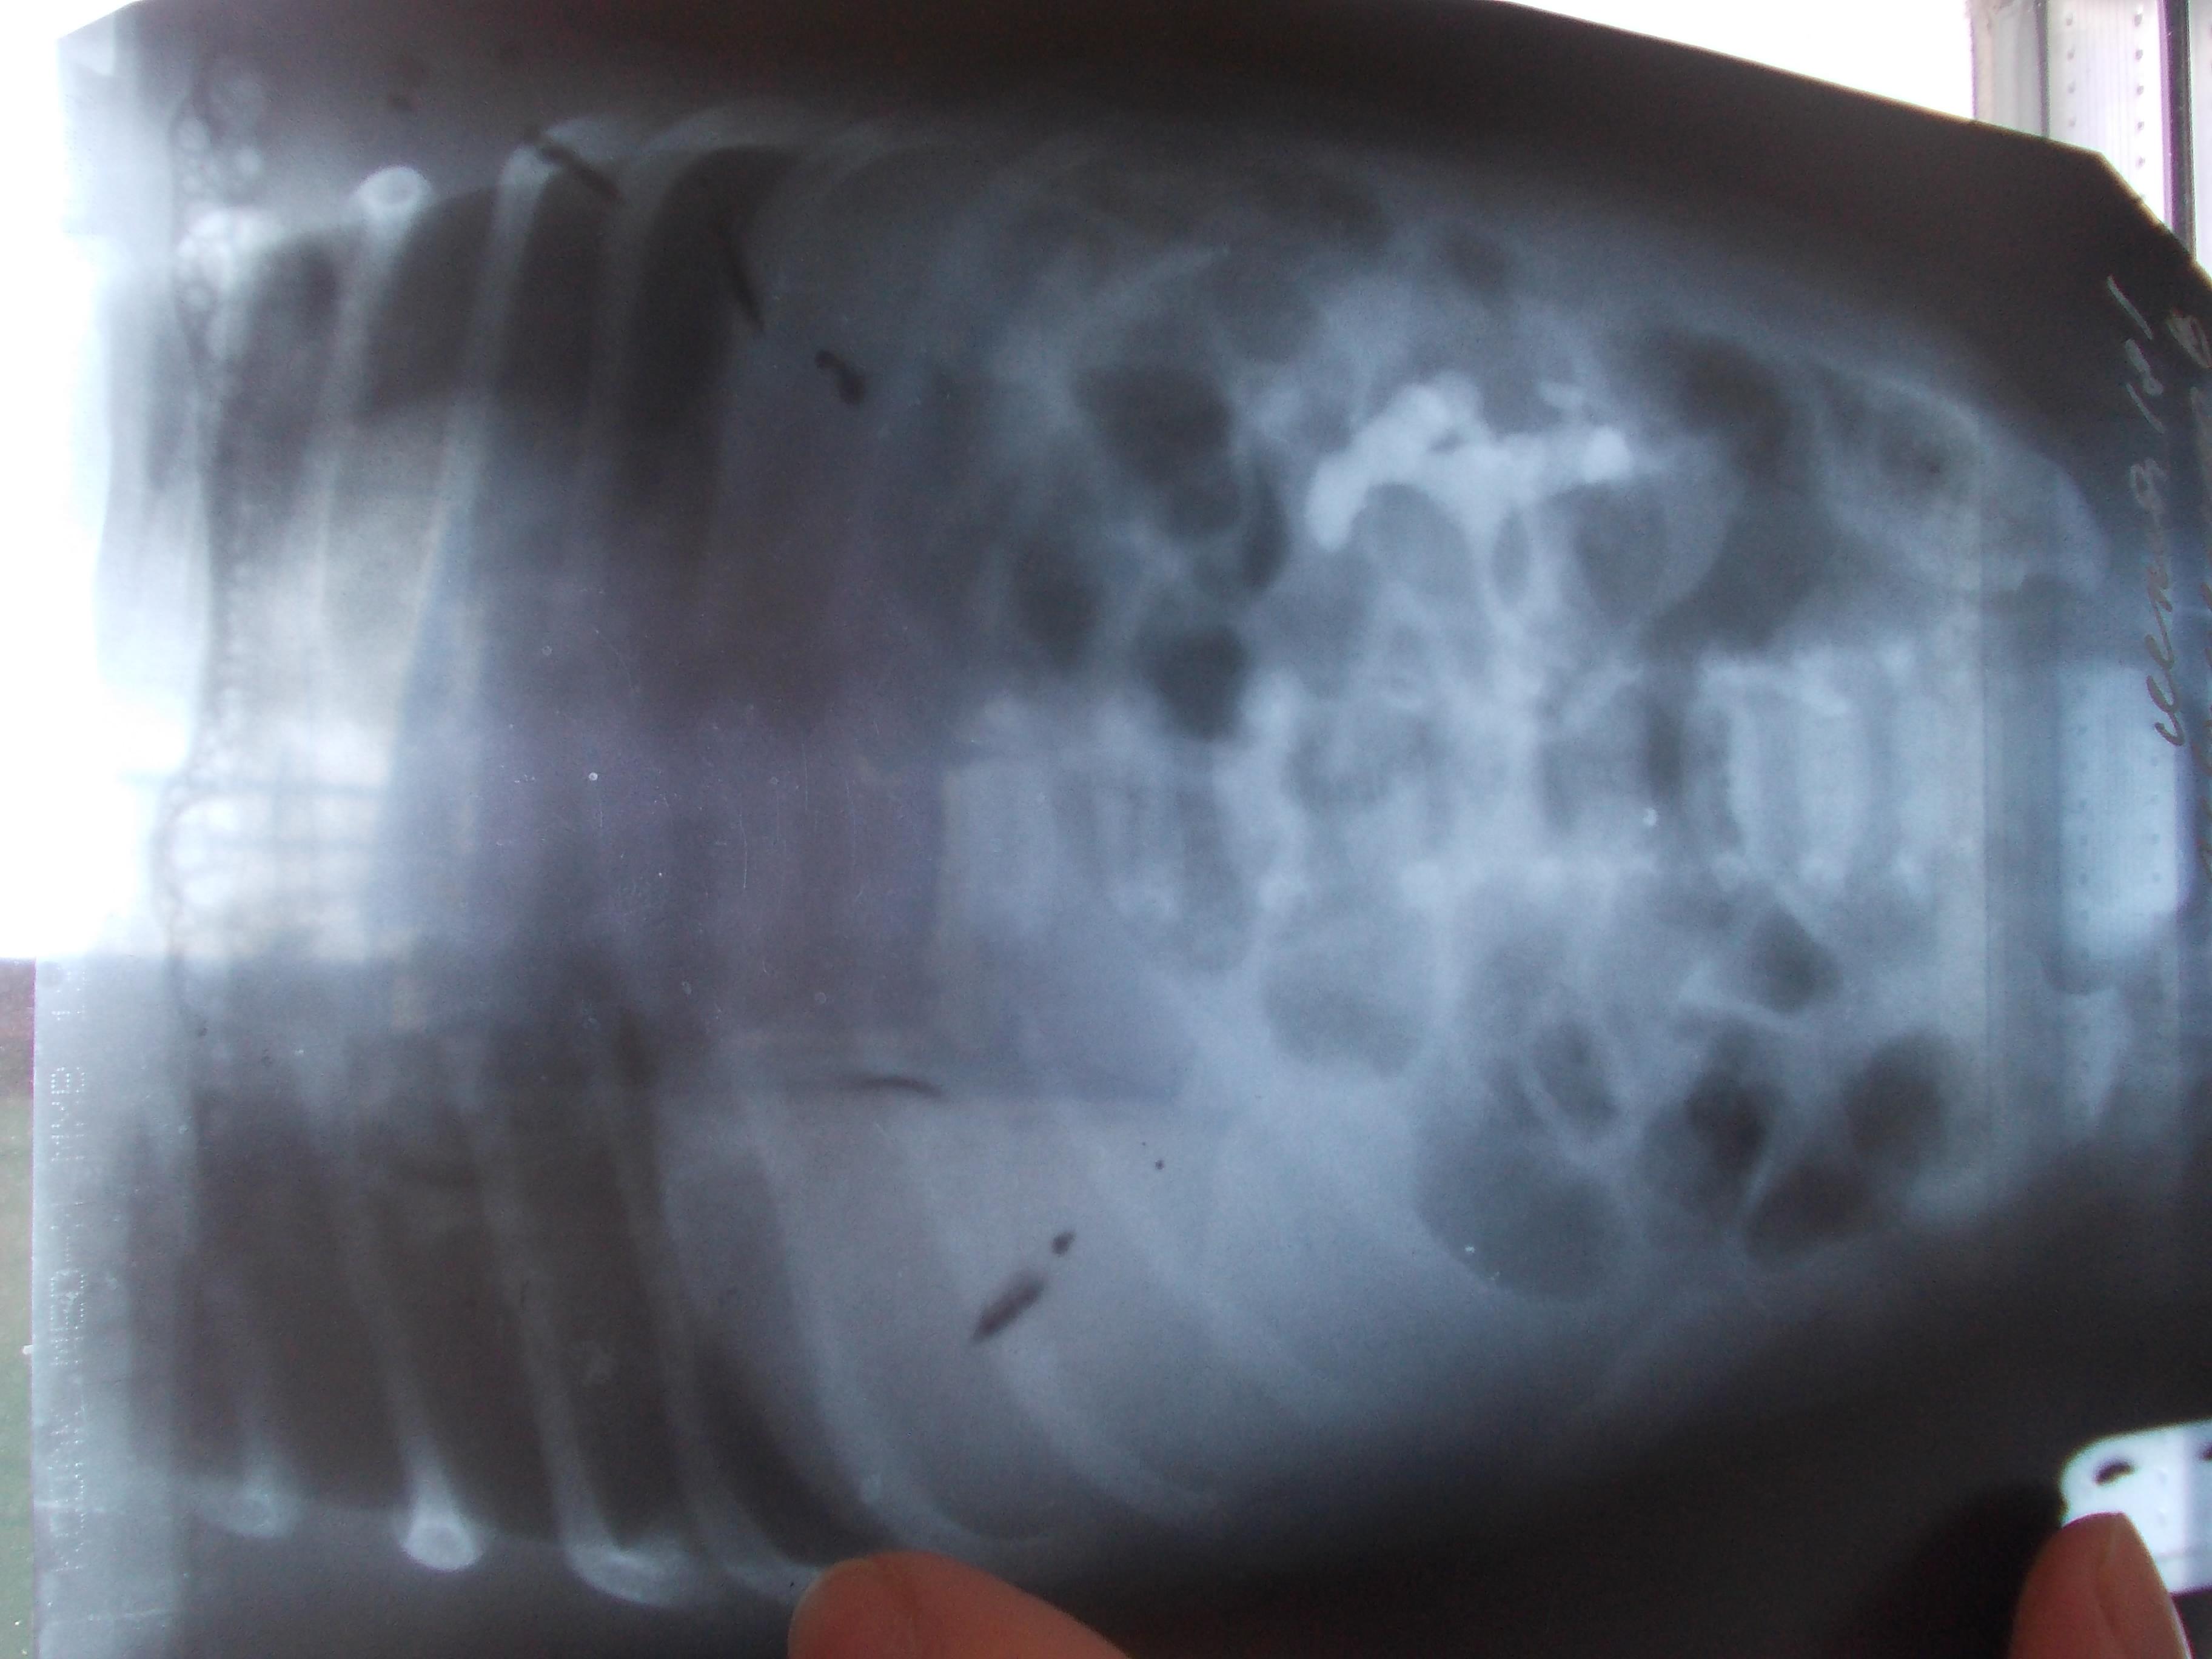

Здравствуйте Татьяна Николаевна! Спасибо что откликнулись на мой запрос. Направляю Вам результаты УЗИ и фото снимков урографии (в приложении «УЗИ и снимки »). После выписки из роддома ребенок был направлен в отделение патологии новорожденных, где и прошли обследование . Из выписки следует что:

- по результатам внутривенной урографии от 21.04 – нефункционирующая почка справа. Пиелоэктазия слева. Контроль в 1 год. Контроль УЗИ почек в 3 месяца.